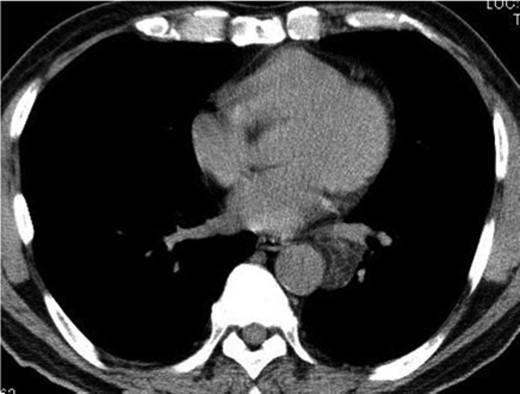

A 74-year-old man was referred to our hospital after a left middle and posterior mediastinal tumor was detected on computed tomography (CT) performed as an examination for dry cough in other hospital. CT about 2 years earlier had shown a 3.2 × 2.4-cm lipomatous tumor at the left hilum adjacent to the left lower pulmonary vein (Fig. 1), and that lipomatous tumor was considered the origin of the present mediastinal tumor. Contrast-enhanced CT performed in our hospital showed a heterogeneous tumor, displacing the left lower lobe of the lung, and measuring 10 × 7.4 × 6 cm on horizontal and coronal sections (Fig. 2A and B). Magnetic resonance imaging showed a hyperintense marginal region with central hypointensity on T1-weighted imaging, and heterogeneously high intensity in the whole tumor on T2-weighted imaging. We scheduled surgical resection, and the patient was admitted to our hospital 3 weeks after the first visit. Chest radiography showed rapid growth of the left intrathoracic tumor (Fig. 3A and B), and CT revealed a tumor measuring 11.4 × 8 × 6.2 cm without pleural effusion or hemothorax.

CT from another hospital 2 years earlier shows a 3.2 × 2.4-cm lipomatous tumor at the left hilum adjacent to the left lower pulmonary vein.